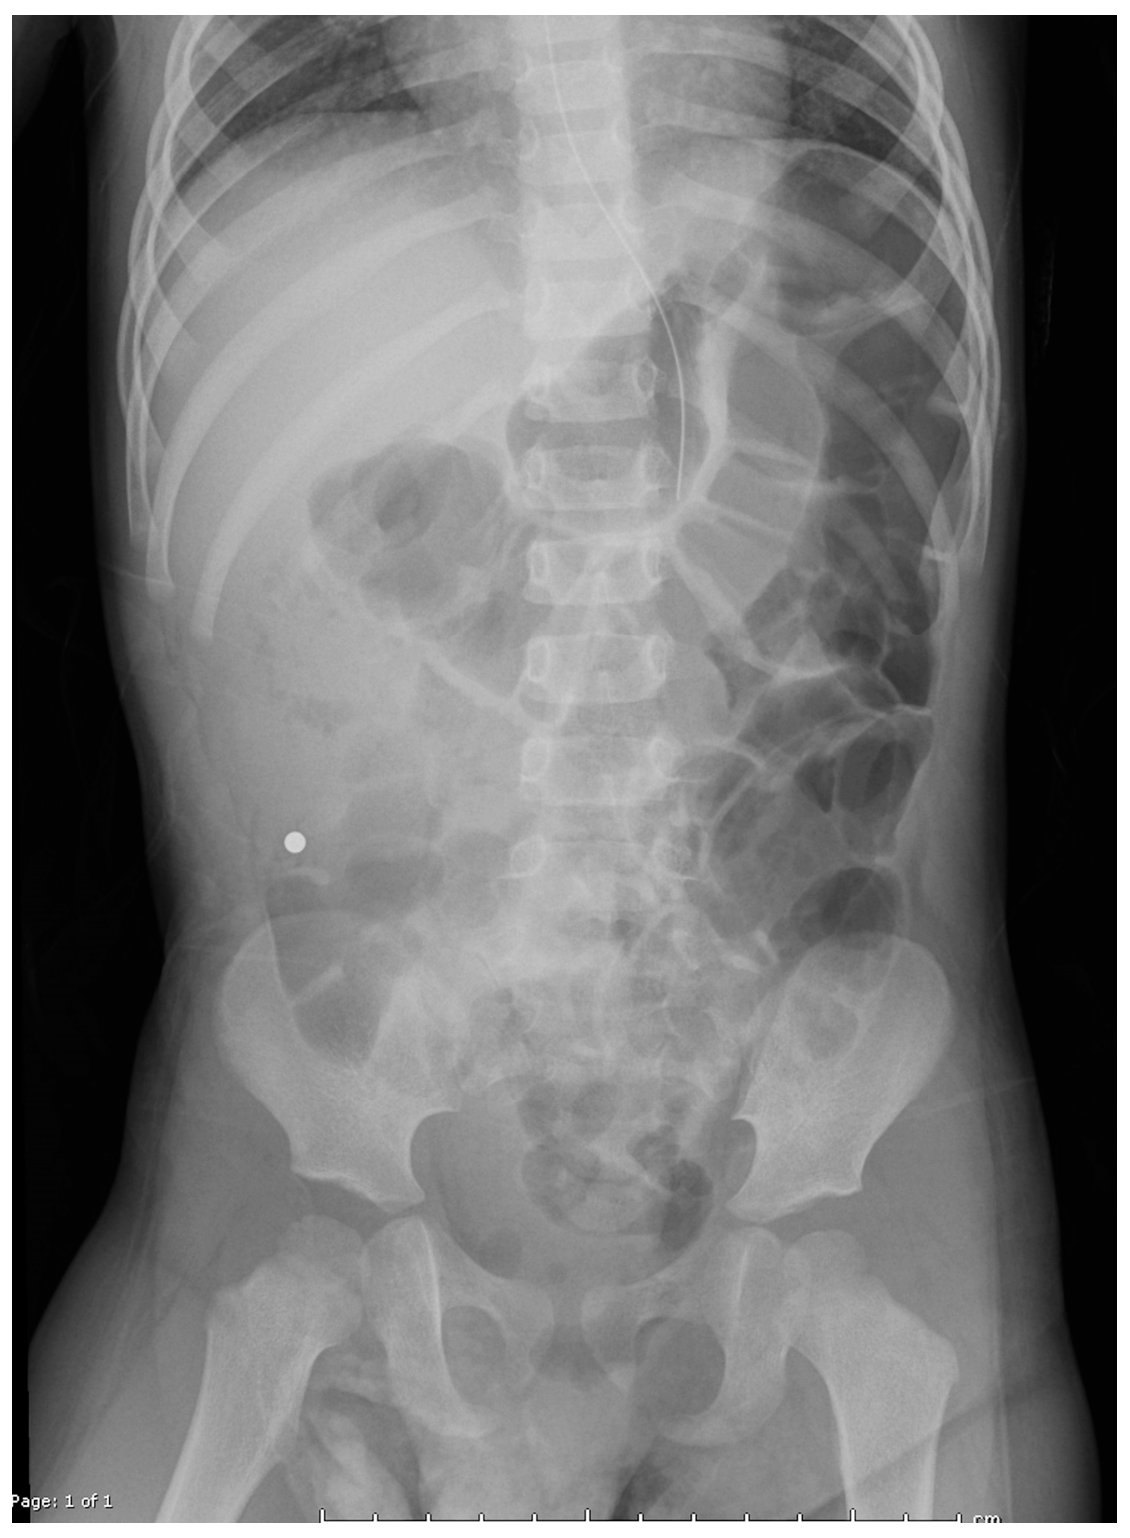

Plain radiographs demonstrated metallic densities clustered in the oropharynx, stomach, and small bowel (Figure 1). Recognizing the risks of gastrointestinal perforation and necrosis, the ED team initiated immediate multidisciplinary consultations with otolaryngology, gastroenterology, and general surgery. Magnet ingestions have been increasingly reported in pediatric literature due to their accessibility and the unique risks they pose to gastrointestinal tissues [4,5,6,7,8,9,10].

Figure 1. The radiograph from outside hospital reveals two magnets trapped in the oropharynx, with additional magnets overlying the distal stomach and proximal small bowel.